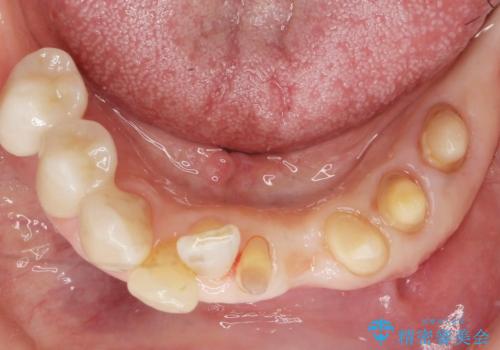

精査したところ、前歯の咬み合わせが反対になっていること、下の奥歯(下顎両側67)が4本欠損していることから動揺が生じていました。

入れ歯も抵抗があるとのことから、相談を重ね、今の状態では保存不可能な下の前歯(左下2)を抜去し、ブリッジや連結補綴により動揺を抑えることにしました。

下顎大臼歯が欠損したままで今ある歯に負担がかかりやすいことから、長期的予後は保証できないことをご理解頂いた上で治療を行いました。

- ¥1,110,000 (根管治療×1本、土台×2本、仮歯×9本、クラウン×9本)費用は治療当時の料金となります